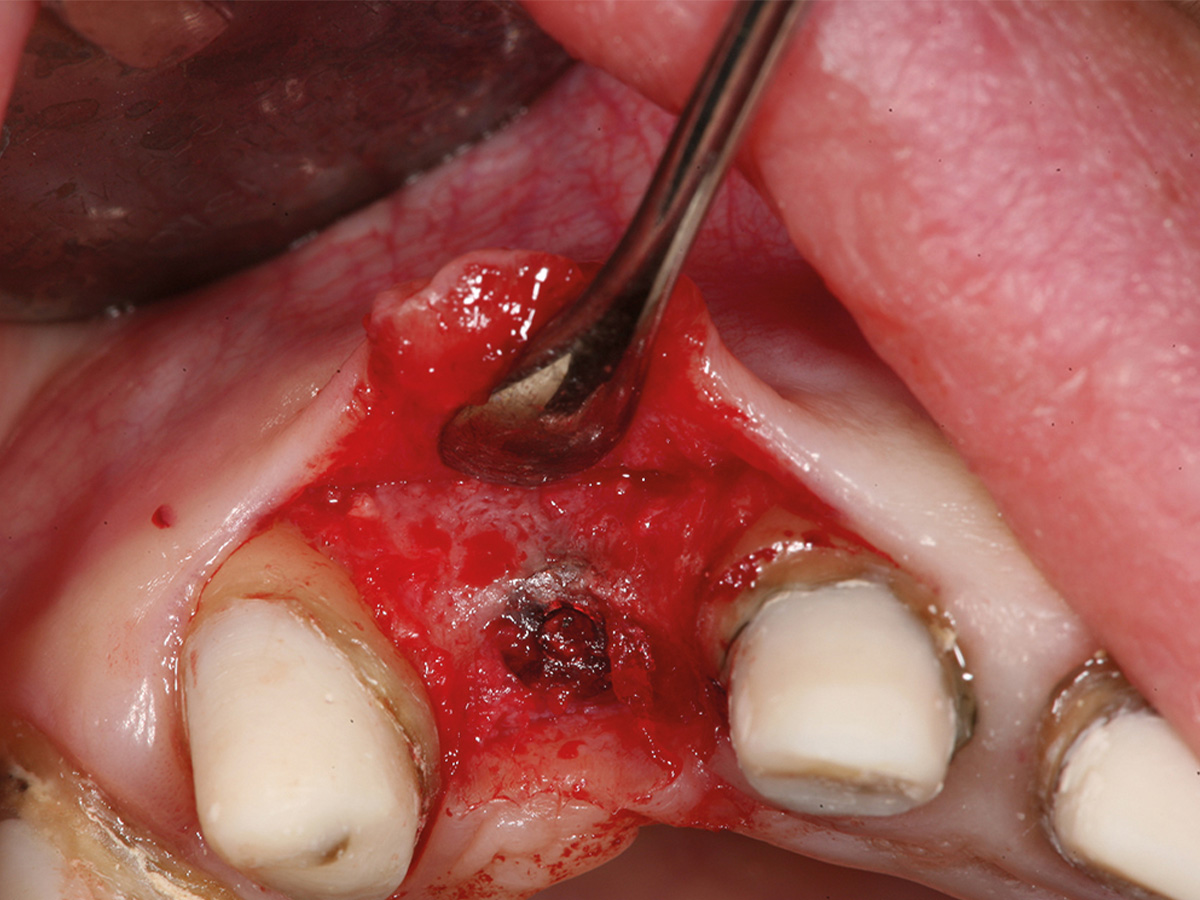

Abbildung 7

Situation 1 Woche post-OP mit Provisorium.